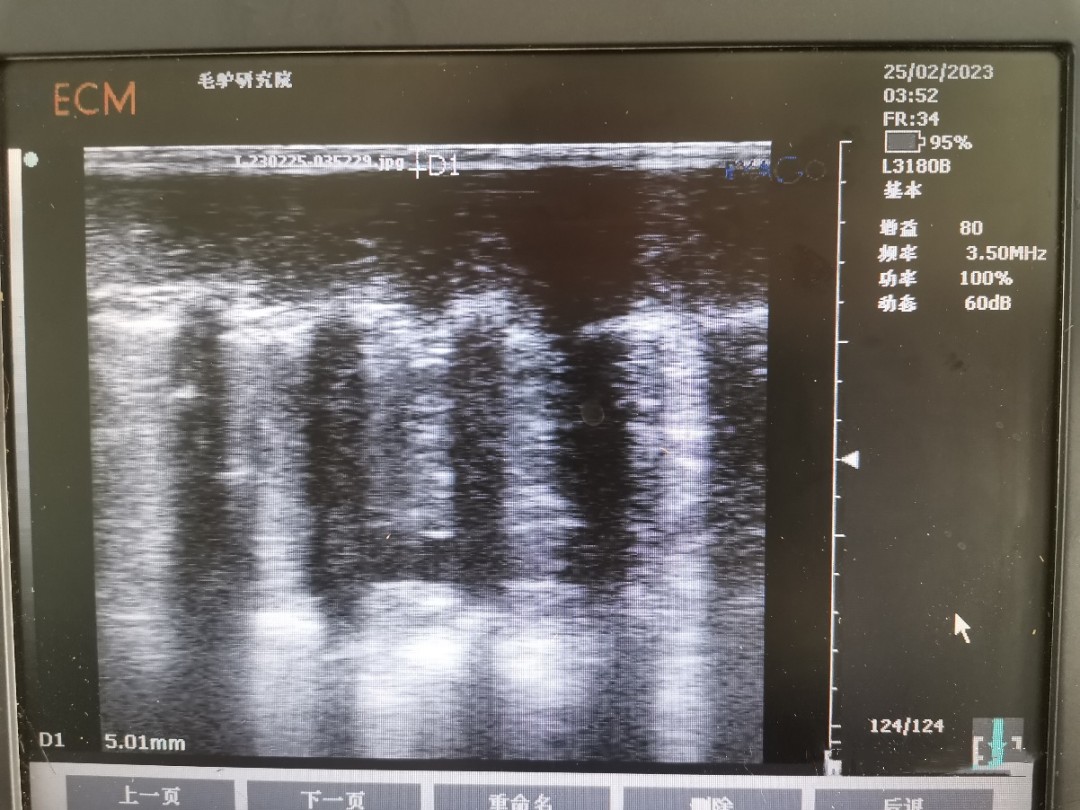

背膘活體測定可反應(yīng)家畜的膘情,而家畜的膘情與繁殖性狀相關(guān)。已有研究表明,豬的背膘和眼肌面積的研究已經(jīng)非常成熟,豬的背膘厚與繁殖性狀相關(guān),眼肌面積與生產(chǎn)性狀相關(guān)。同時,近年來在牛上也陸續(xù)開展背膘和眼肌面積工作的測定。背膘厚度及眼肌面積的活體測定,在指導(dǎo)動物的生產(chǎn)、精準飼喂、動物的遺傳改良中發(fā)揮較好作用,使家畜育種和生產(chǎn)工作取得了較大進展。但此技術(shù)在驢上應(yīng)用卻較少。

為了彌補背膘和眼肌面積在驢上的應(yīng)用空白,我團隊開展了德州驢背膘和眼肌面積的測定工作。為更好的驗證所測定的結(jié)果,團隊成員在已屠宰的德州驢上進行確認,確保測量結(jié)果準確性。背膘厚及眼肌面積性狀在驢遺傳育種上的應(yīng)用將為選育更加優(yōu)良的德州驢種質(zhì)提供了新的指標,可加快驢種質(zhì)創(chuàng)新步伐。